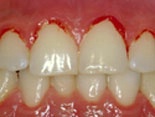

Inflammerat tandkött

tdl9Blödande tandköttEn inflammation i tandköttet kan vara början till parodontit. Och det är placket som bildas i munnen som är orsaken till tandköttsinflammation (gingivit). Inflammation utan parodontit är enkel att behandla. Med förbättrad munhygien läker det oftast ut på en eller ett par veckor. Dock kan inflammationen komma tillbaka snabbt om munhygienen försämras. Noggrann rengöring med tandborste, tandtråd eller liknande är det enklaste knepet för att undvika inflammerat tandkött.